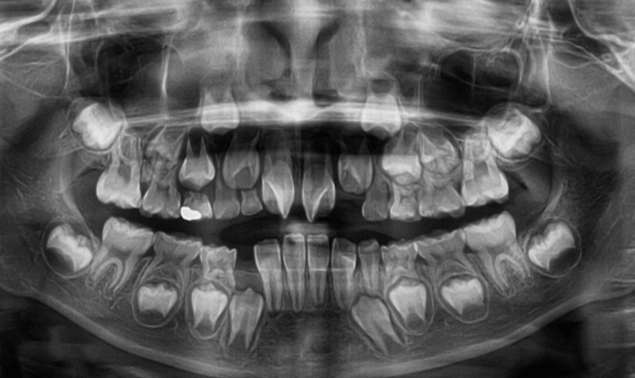

| 年齢・性別 | 8歳9ヶ月の男児 |

|---|---|

| 主訴 | 前歯の咬み合わせが逆になっており、歯根や歯肉への影響を懸念されて来院された患者様です。 |

| 治療期間・回数 | 3年7ヶ月・20回 |

| 費用 | 460,000円(税別) |